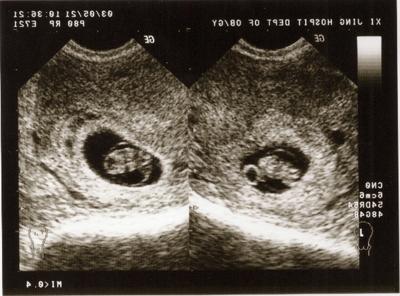

怀孕早期B超:停经6周后

在停经6周后,除了妇科常规检查之外,应通过B超确定宫内妊娠是否正常。例如宫腔内探查不到任何妊娠征象,而在子宫腔外探到异常的包块,结合其他的临床表现和实验室检查结果就可以考虑宫外孕可能。所以一般提倡于怀孕早期通过做B超明确是否是正常妊娠或双胎、葡萄胎等。

1、胎囊(GS)

胎囊也叫孕囊,胎囊只在怀孕早期见到。月经28~30天规则来潮的妇女,停经35天,B超就可以在宫腔内看到胎囊。

胎囊的位置:胎囊位置在子宫的宫底、前壁、后壁、上部、中部都属正常;形态圆形、椭圆形、清晰为正常;如胎囊为不规则形、模糊,且位置在下部,孕妇同时有腹痛或阴道流血时,可能要流产。

胎囊的大小:怀孕6周时胎囊直径约2厘米,孕10周时约5厘米,孕1.5个月时直径约2厘米,2.5个月时约5厘米为正常。